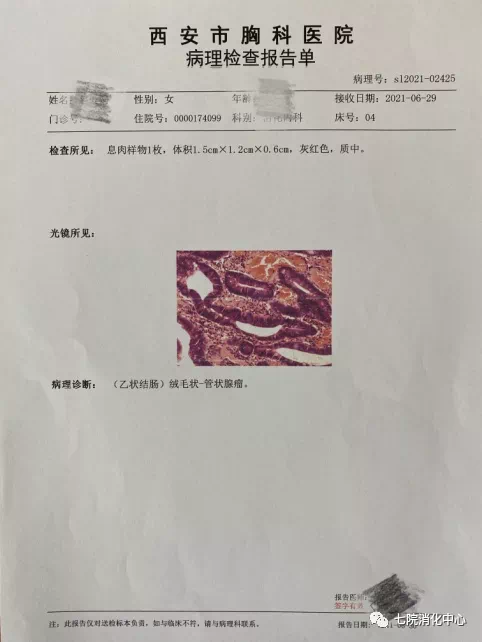

王阿姨今年65岁,前段时间总感觉肚子不舒服,大便带血,每天的排便习惯也有改变,于是来到交大附属胸科医院消化中心就诊,接诊的消化科副主任张蓉在了解其病情后,将其收治入院。入院后肠镜检查发现,其肠道内多发大小不等息肉,最大直径1.8cm.医生当即对息肉进行了切除处理,病理提示管状绒毛状腺瘤伴低级别上皮内瘤变,但庆幸的是发现较早,目前王阿姨已经康复出院,之后只需要每半年复查一次肠镜。